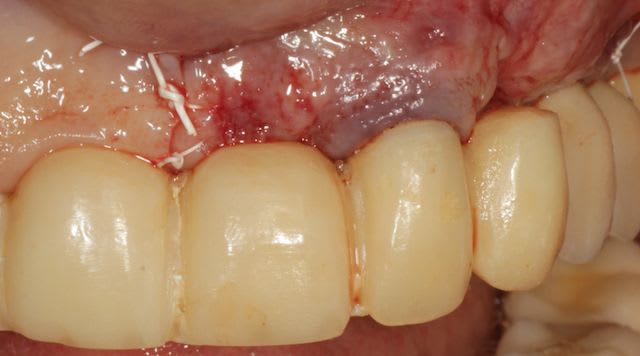

Grosse perte osseuse au niveau de la 23, ROG avec Bio-Oss et autogène dans un rapport 50/50, le tout recouvert pas une BIo-gide maintenu avec de pin's.

Belle chirurgie. J'apprecie particulièrement tes tracés d'incision : on voit que tu mènes une chirurgie réfléchie et le soin que tu portes aux tissus parodontaux est juste. Tu es rigoureux avec les autres mais également avec toi-même et c'est tout en ton honneur !!

Tu sais le lambeau est replacé parfaitement et suturé soigneusement une fois que la chirurgie est terminée : vraiment aucune complication à craindre à ce niveau, surtout pas quand les tissus ont été manipulés avec un tel soin : incision franche, élévation propre, aucune déchirure, suture impeccable.

Désolé pour le retard, je vais essayé de répondre à tout le monde, mettre un implant et faire une ROG de façon predictible dans un cas comme ça c'est impossible, la photo pré-op c'est la dernière ( je ne sais pas pourquoi nonol m'a inversé l'ordre ), à noter que j'ai fait ce design d'incision car 24 et 25 sont des implants et je ne voulais justement pas me retrouver avec une récession.

J'ai utilisé du BIo-Oss et de l'autogène prélevé avec un scraper à la mandibule, le tout recouvert par une Bio-Gide maintenu par des pin's, suture avec du Gore Tex ( e-PTFE ) et du Cytoplast (PTFE )